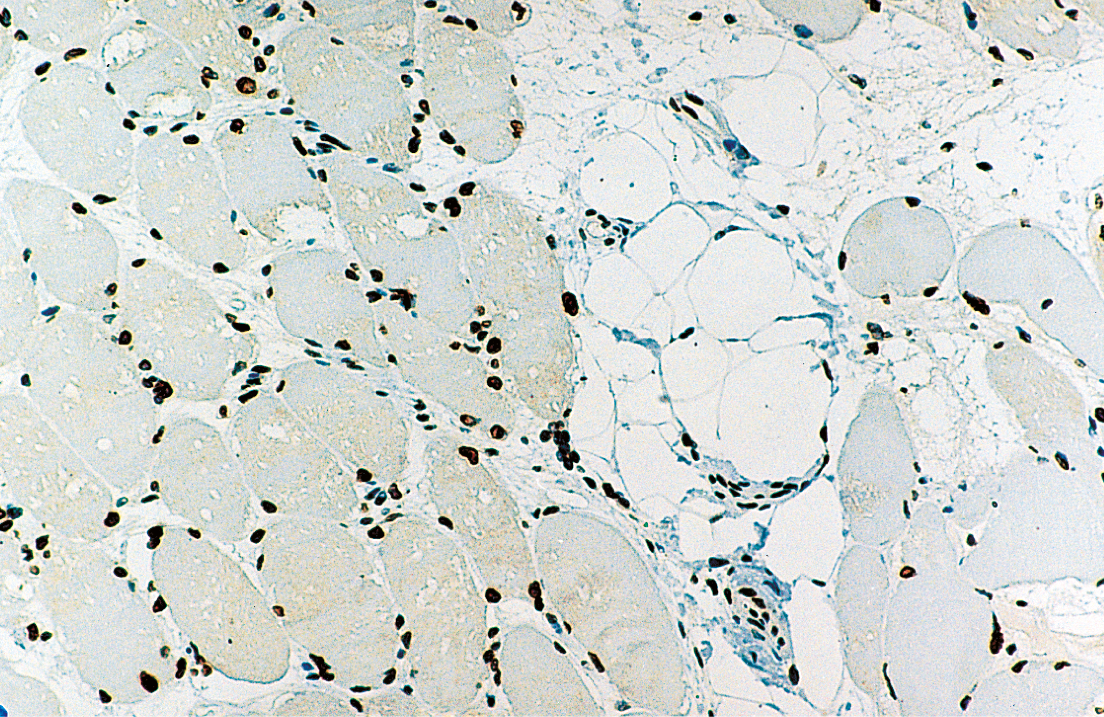

Human skeletal muscle: immunohistochemical staining for Emerin. Note perinuclear staining of all cell nuclei. Emerin: clone 4G5